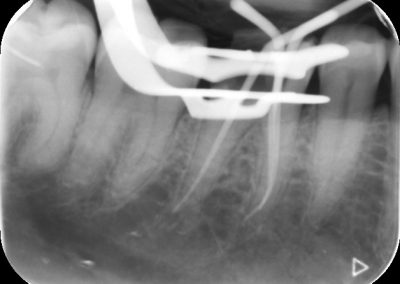

Before commencing the treatment, a local anaesthetic is administered and later a protective non-latex rubber sheet is placed around the tooth to prevent saliva contaminating the tooth and at the same time improves patients comfort.

An access cavity is placed on the surface where the patient bites, to reach the root canals of the tooth. Once all the canals are identified, small files are used to remove the infected pulp.

Files of different sizes are used to eliminate bacteria and infection and to shape the canals. The canals are disinfected thoroughly with irrigants and later the canals will be sealed in 3 dimensions with a special medicament called gutta-percha to prevent reinfection of the tooth and the access cavity will be sealed with a temporary filling.